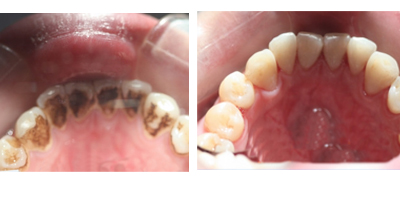

去除牙结石更有效的方法就是洗牙,赵德彪医生推荐萧先生采用喷砂洁牙深层洁牙护理。该技术不但能够清洁牙齿,还可以对牙齿抛光和全方位牙检,喷砂洁牙利用频率28kHz以上的超声波震动来彻底洁治,仅需15分钟即可达到清洁牙齿的功效,让洁牙变成一种享受。该技术的碳酸钙喷砂粉全面取代传统碳酸钠喷砂粉,具有圆滑柔和、无咸味、无涩感、恒温,无酸痛感,彻底快速等多项特点。

3、洗牙:洗牙前后超声波洗牙,是针对清除牙齿结石部份。因为牙结石更容易造成牙菌班的堆积,造成牙龈炎、牙龈出血,牙周病。所以去除牙结石是医疗行为。当然在治疗的同时,齿颈部,邻接面的结石去除掉了,牙齿也会有美白的表现。洗牙的弊端在于比较痛,会出比较多的血,还有洗后牙齿表面比较粗糙,牙渍牙石的再次出现更加来得快。更后就是有可能感染疾病。